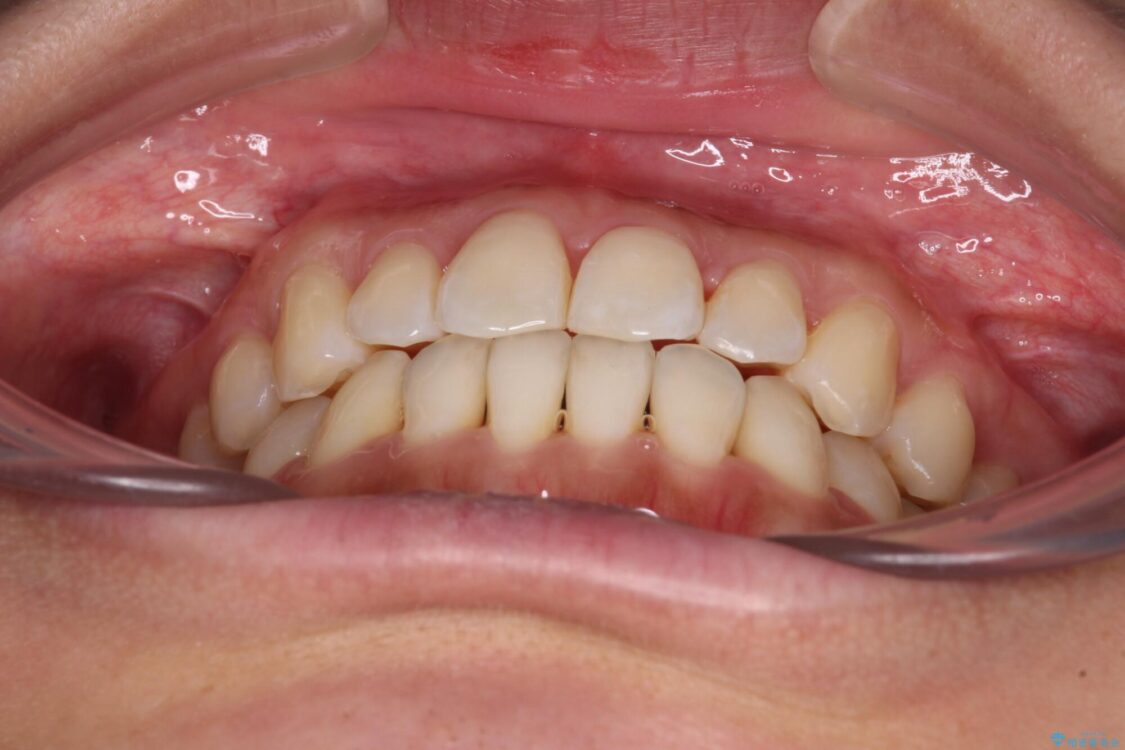

治療後について

装着時間を守ってくださったので、予定通りの期間で終えることができました。インビザライン特有の、奥歯の咬み合わせの問題もなく、しっかりと歯列を改善することができました。

治療後

• 【モニター】前歯のデコボコをインビザラインで改善 治療後画像